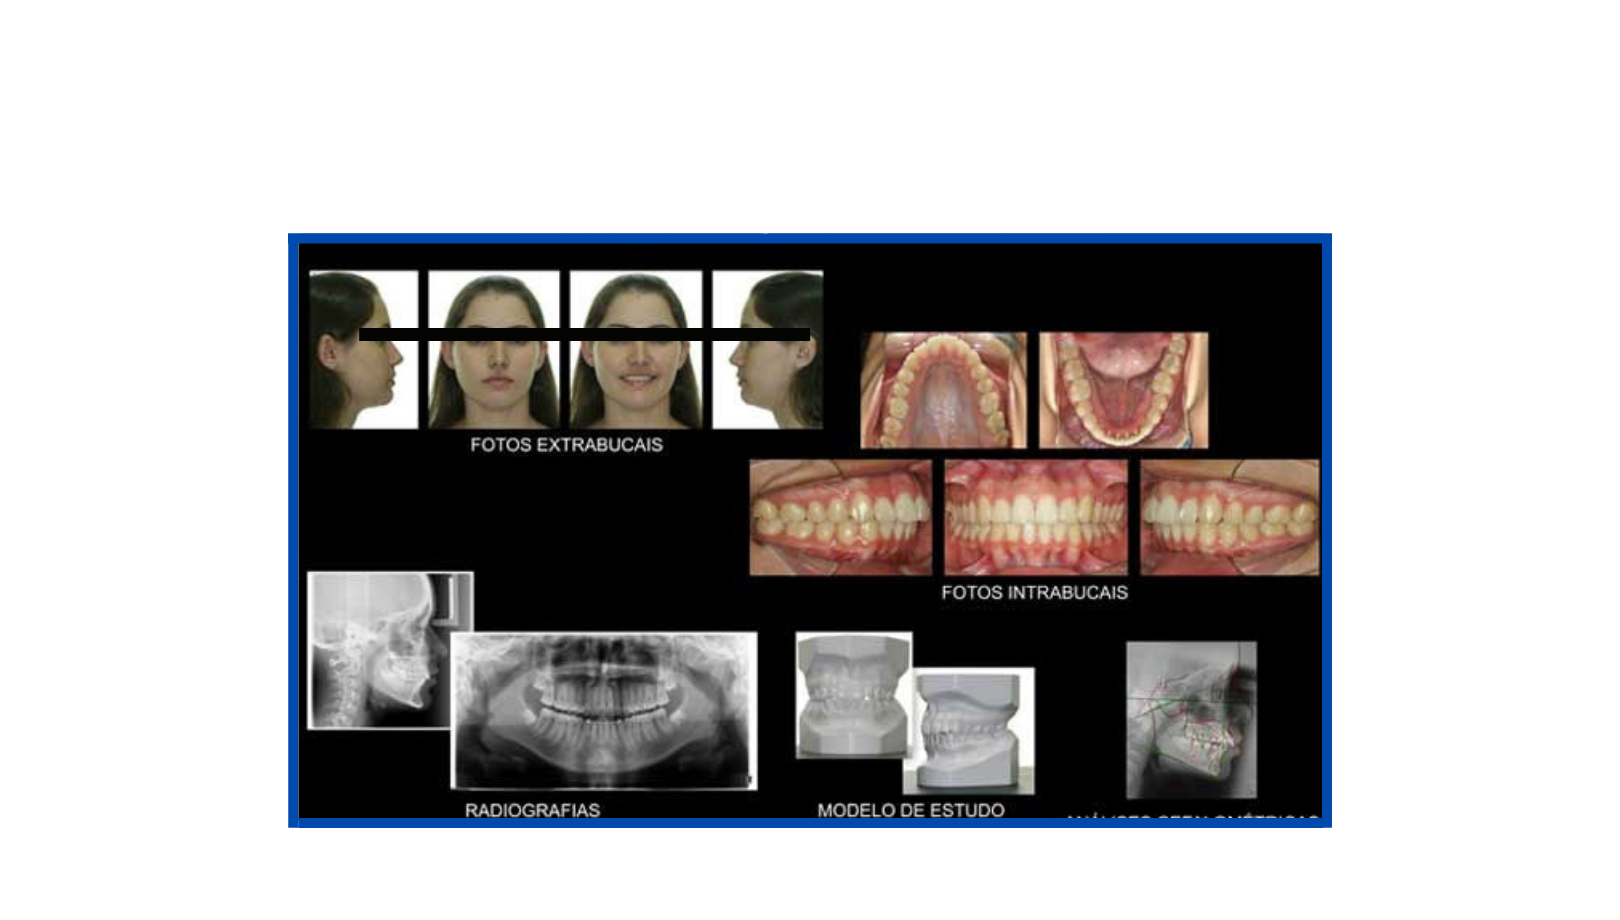

Documentações Ortodônticas

A documentação ortodôntica é um conjunto de exames composto por radiografias, fotografias intra e extra-bucais, modelos em gesso das arcadas dentárias, análises cefalométricas e de modelos computadorizados que o dentista solicita para ter uma visão abrangente e detalhada do caso de seu paciente.